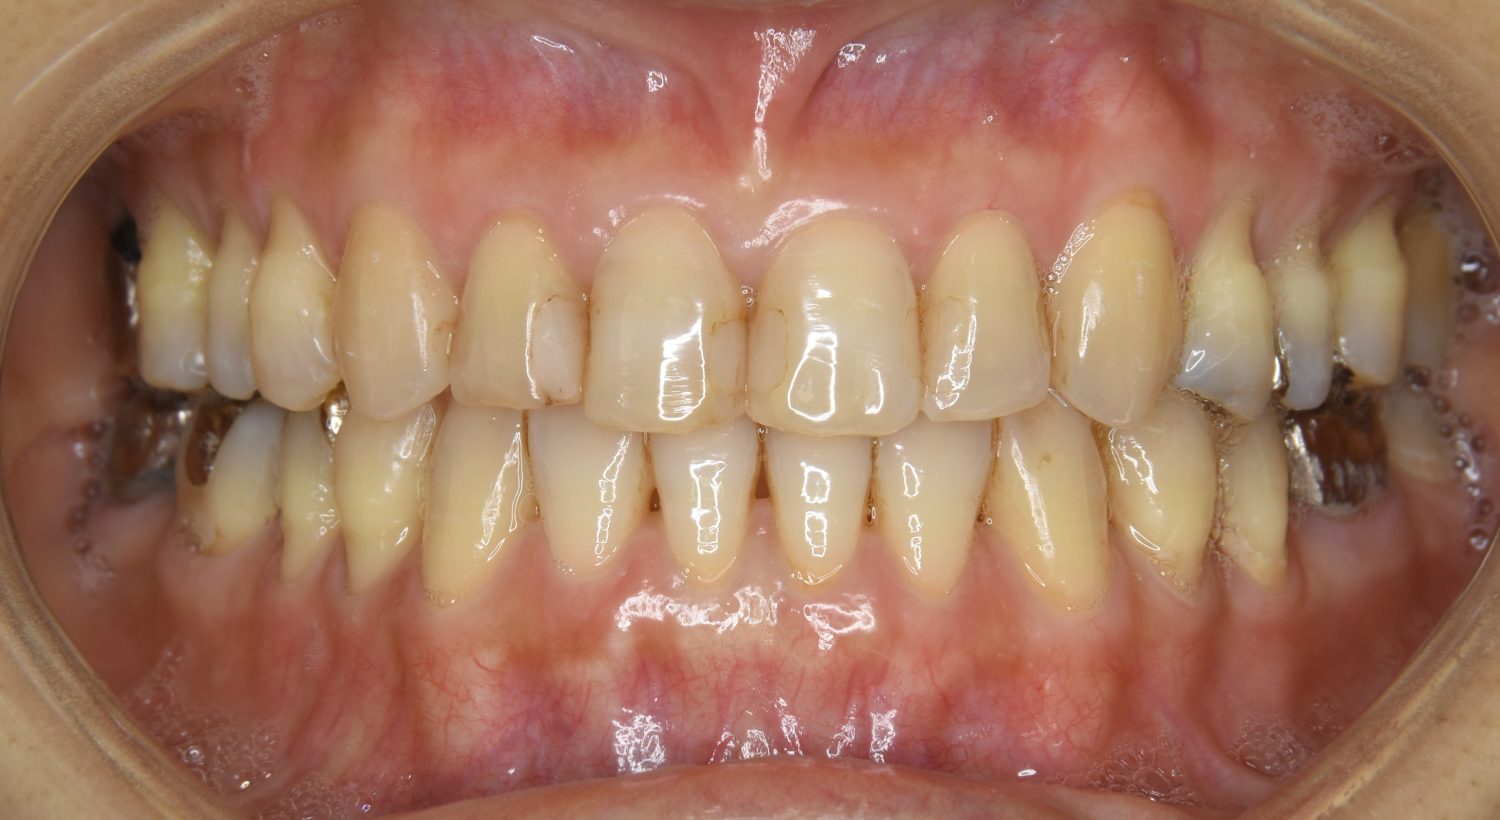

前歯部開咬の症例紹介②

Before

主訴

前歯で物が噛めない

治療内容

上下ラビアルブラケット(唇側装置)に矯正用アンカースクリューを併用し非抜歯で治療を行いました。

上下の前歯が開いており前歯では全く噛めていない状態でした。臼歯の圧下を行うことで機能面のみでなく審美面も改善しました。